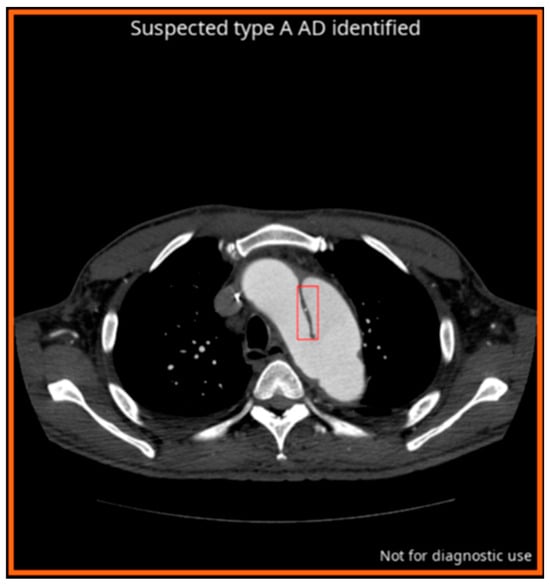

- Laletin, V.; Ayobi, A.; Chang, P.D.; Chow, D.S.; Soun, J.E.; Junn, J.C.; Scudeler, M.; Quenet, S.; Tassy, M.; Avare, C.; et al. Diagnostic Performance of a Deep Learning-Powered Application for Aortic Dissection Triage Prioritization and Classification. Diagnostics 2024, 14, 1877. [Google Scholar] [CrossRef]

- U.S Food & Drug Administration. BriefCase for AD, K222329; 510(k) Premarket Notification; U.S Food & Drug Administration: Silver Spring, MD, USA, 2022.